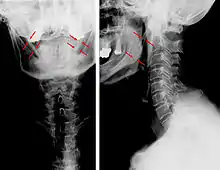

| Anteroposterior and lateral radiographs of cervical spine showing ossification of the stylohyoid ligament on both sides | |

Imaging is important and is diagnostic. Visualizing the styloid process on a CT scan with 3D reconstruction is the suggested imaging technique.[12] The enlarged styloid may be visible on an orthopantogram or a lateral soft tissue X ray of the neck.